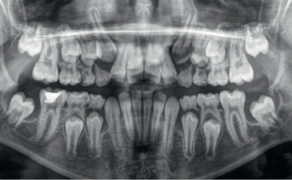

Streszczenie: W pracy przedstawiono postępowanie kliniczne u pacjentki z obustronnym wrodzonym brakiem siekaczy żuchwy. Ten stan jest stosunkowo rzadki i zawsze wymaga dokładnego rozpoznania i planowania leczenia. Wybrana dla pacjentki strategia leczenia obejmowała zamknięcie przestrzeni poprzez protrakcję tylnych zębów żuchwy i zastąpienie brakujących siekaczy kłami. Ponadto omówiono problemy wynikające z takiego planu leczenia, takie jak okluzja chroniona przedtrzonowcami i rozbieżność wielkości zębów. W oparciu o przypadek przedstawiony w niniejszej pracy można wnioskować, że zamknięcie przestrzeni można uznać za skuteczne podejście terapeutyczne, pozwalające na uzyskanie zadowalających wyników funkcjonalnych i estetycznych.

Hipodoncja jest definiowana jako wrodzony brak jednego lub kilku zębów [1]. Cięższymi postaciami agenezji zębów są oligodoncja i anodoncja, charakteryzujące się odpowiednio brakiem więcej niż sześciu zębów i całkowitym brakiem zębów. Są one zwykle związane z innymi schorzeniami ogólnoustrojowymi, takimi jak: zespół Downa, dysplazja ektodermalna i zespół Ellisavan Crevelda [1, 2]. Istnieją cztery główne teorie dotyczące etiologii agenezji zębów; może być ona traktowana jako manifestacja trendu ewolucyjnego lub może być spowodowana czynnikami środowiskowymi albo ogólnoustrojowymi, takimi jak: uraz, stan zapalny, zakażenia kości szczęki/żuchwy czy też zaburzenia hormonalne [...]